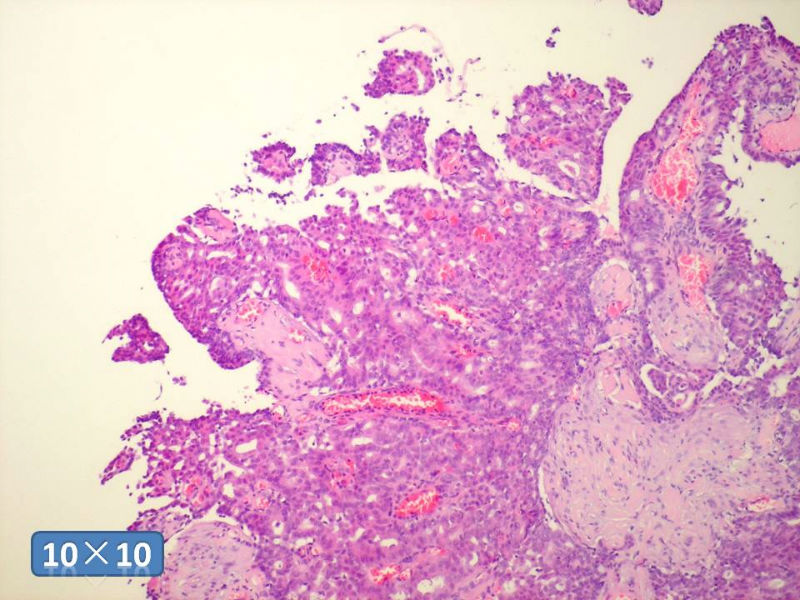

只能说是乳头状瘤

是不是导管内

乳头状瘤 and 导管内乳头状瘤 are the same; Benign lesion.

After you work up and you still cannot be sure it is benign , atypical or maignant lesion, you can call 乳头状lesion.

If this is excisonal case, you should figure out the nature of the papillary lesion.

我的意思就是提醒大家 在不是很确定的情况下 尽量少给自己套枷锁